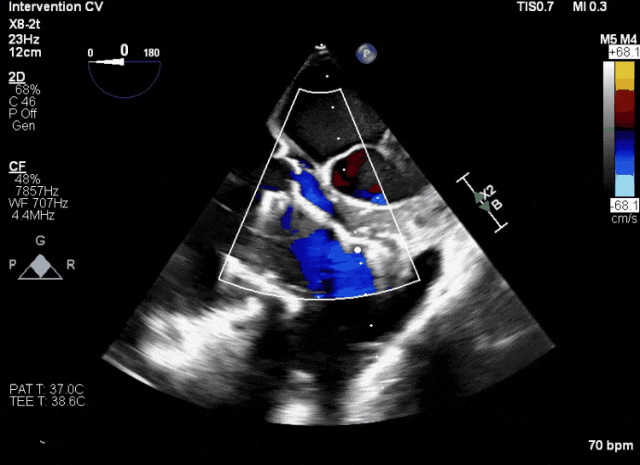

術后DSA、超聲顯示人工瓣膜穩(wěn)定性良好,瓣葉啟閉正常,無瓣周漏